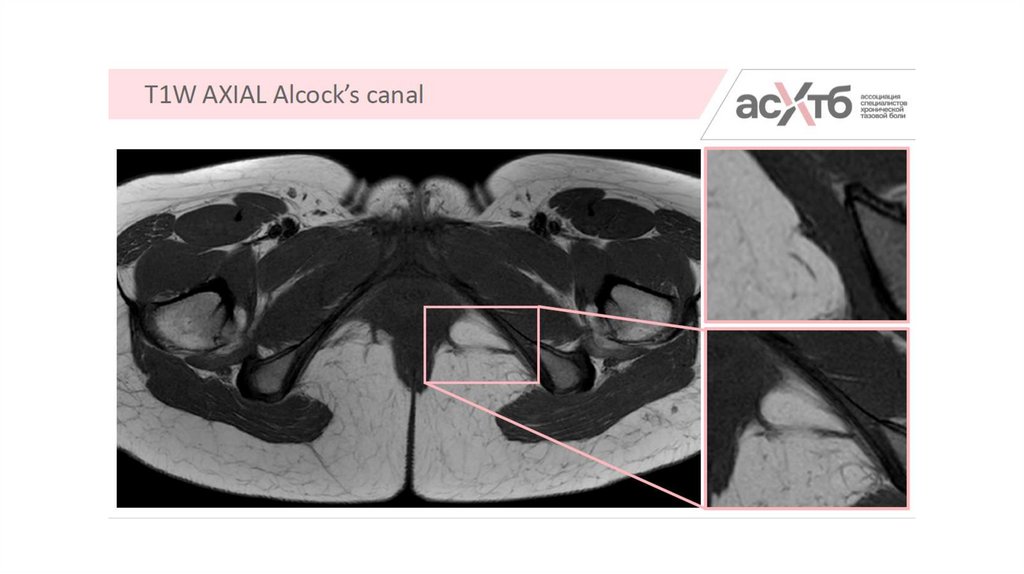

5.

7. МР-нейрография

8. Режимы

• Для полового НЕЛЬЗЯ! Ввиду ограничения визуализации.